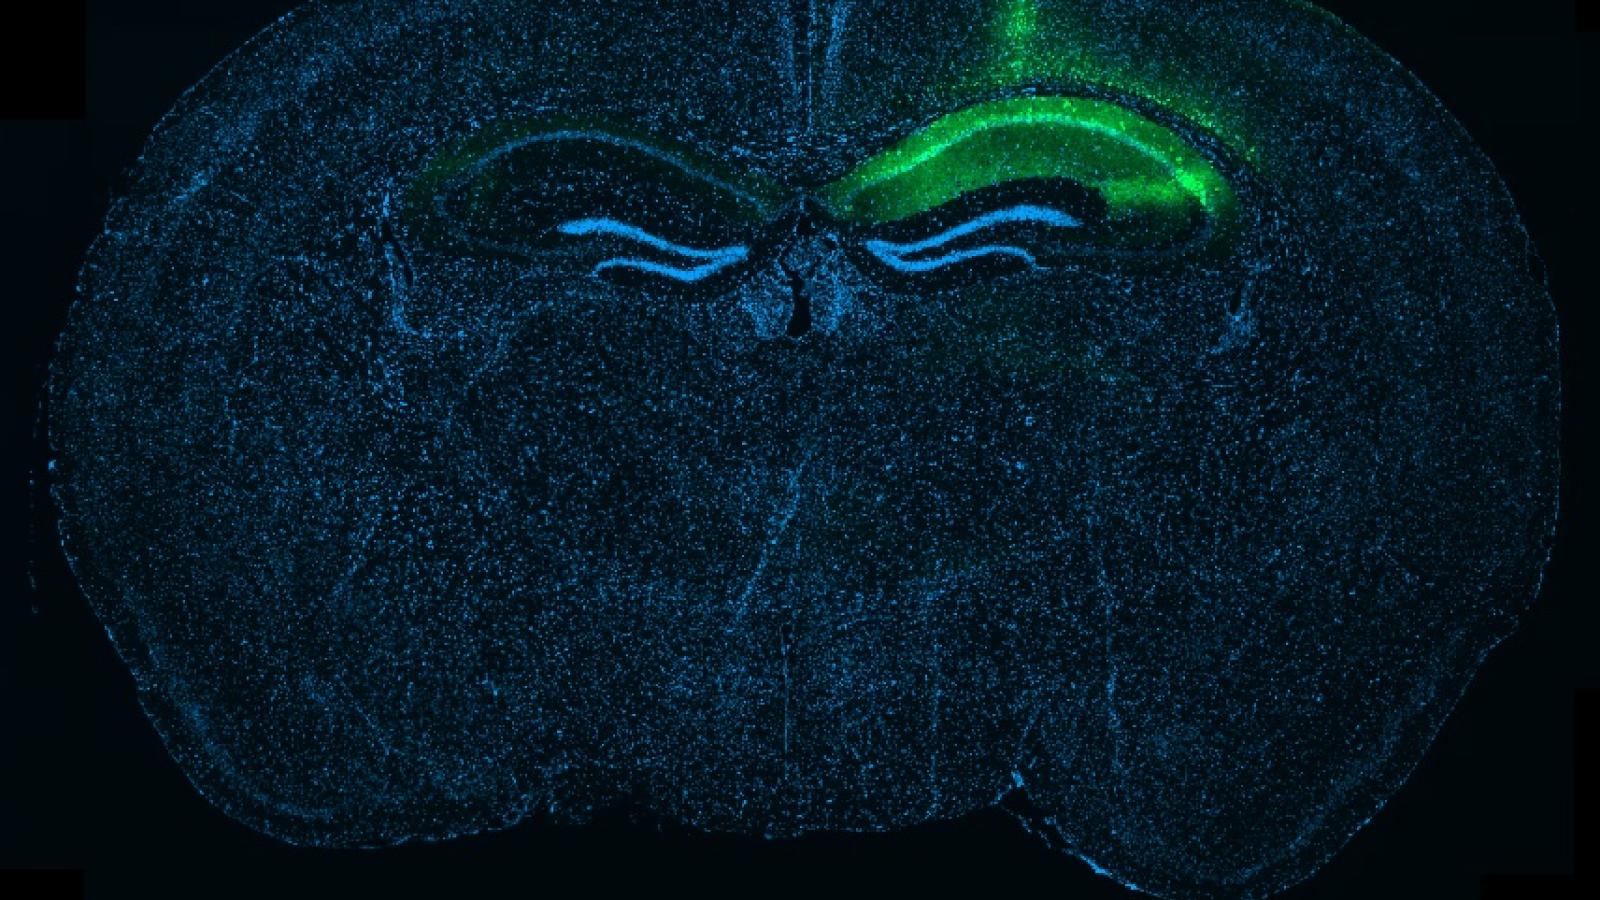

Whole-brain section showing local tau expression in the hippocampus

Banner image: Whole-brain section showing local tau expression in the hippocampus after a targeted injection, visible here as the green signal on one side of the brain. Credit: Robert Ellingford